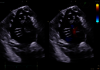

Vous recherchez une solution d’imagerie cardiaque qui allie fiabilité et simplicité d’utilisation. Le système d'échographie ultra-premium Vivid Pioneer se distingue par ses capacités avancées. Il est désormais doté de cSound™ Pioneer, une plateforme de nouvelle génération conçue pour améliorer la clarté et la définition pour tous les type de patients. Avec un traitement d'image amélioré et une formation de faisceau adaptative, elle vous accompagne dans vos diagnostics qu'ils soient standards ou complexes.

Découvrez une clarté et une précision d'image extraordinaires

Conçue pour vous emmener plus loin, la nouvelle génération de cSound Pioneer se combine avec notre technologie de sonde avancée pour fournir des détails améliorés, un nouveau standard de flux couleurs et une incroyable imagerie 4D pour une confiance clinique dès le premier scan.